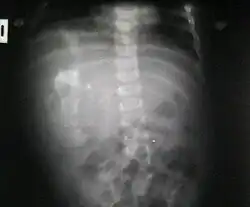

Fetus in fetu

El fetus in fetu es un gemelo parásito[1] o mellizo parásito[1] muy poco desarrollado (ya que no cuenta con órganos internos), una formación humanoide creada por un accidente en cierto punto de la formación del cigoto previo a la formación del embrión.

Ocurre en 1 de 1 000 000 nacimientos,[2][3] y se define como una masa fetiforme totalmente encerrada dentro del cuerpo del autósito o hermano desarrollado. Al extraerse, está envuelto en lo que parece un huevo de gallina, pero mucho más grande y extremadamente duro. El parásito, cuando es extraído y expuesto, tiene un color blanco. Una vez que se extrae, muere, ya que es un tejido totalmente dependiente de su hospedador. Al igual que en los gemelos parásitos, corazón y cerebro están ausentes o son muy rudimentarios. Puede estar más o menos organizado, con características muy variables, desde apenas una bola de tejidos hasta contener restos de pelo, hueso, manos con dedos y uñas y hasta piernas. La extirpación quirúrgica no presenta el menor problema dado que no pasan de ser tumores que pueden llegar a ser un potencial riesgo para su hospedador, debido a que se alimenta de este, representando para el hospedador una carga semiviva sin función en el organismo, y pueden llegar a malignizar.[4]